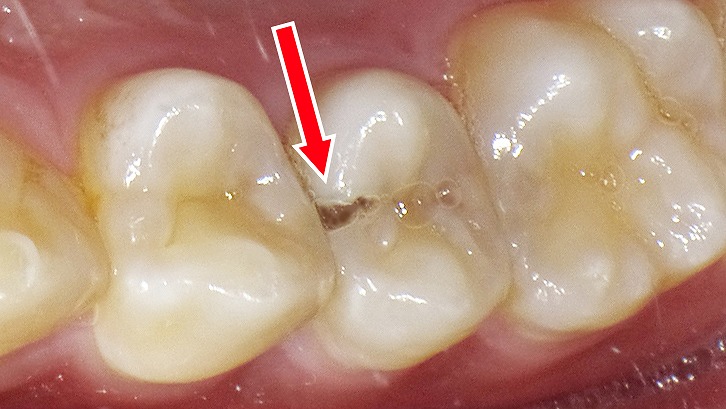

虫歯による穴:症例1

この画像は、上顎の小臼歯部を咬合面から撮影した口腔内写真です。

🔍 解説

赤い矢印で示されているのは上顎第2小臼歯(5番)の近心側(前方側の面)です。

その部分に、黒く変色した小さな穴が確認されます。これは虫歯(う蝕)によって形成された実質欠損です。

🦷 詳細説明

- 虫歯は隣接面(歯と歯の間)に発生しやすく、歯ブラシの毛先が届きにくいため、進行してから気づくことが多い部位です。

- 表面の黒い変色は、エナメル質の崩壊や象牙質への進行を示唆します。

- 初期段階では痛みがなくても、進行すると冷たいものがしみたり、咬むと痛むなどの症状が出る可能性があります。

💡 ポイント

このような小さな虫歯は、早期発見・早期治療が大切です。隣接面う蝕はレントゲンでの確認が有効で、進行度によってはコンポジットレジン修復で対応できます。

定期検診と適切な清掃指導によって、再発を防ぐことができます。